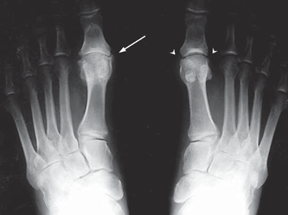

X-ray of Feet With Hallux Rigidus

X-ray of the feet of patient with hallux rigidus. Note the advanced arthritic changes, with large bone spurs and severe joint space narrowing in the left foot (white arrow) and the small spurs with a preserved joint space (white arrowheads) in the right foot.

Reproduced from Advanced Reconstruction Foot and Ankle, p. 45.